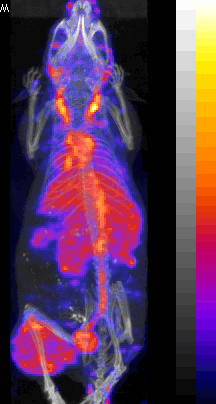

99mTc labeled peptide |

SPECT/CT fusion of 99mTc-MDP Bone Scan